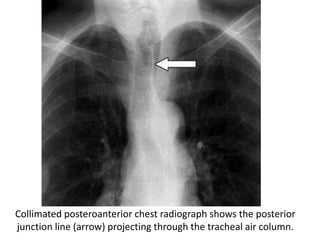

Collimated posteroanterior chest radiograph shows the posterior

junction line (arrow) projecting through the tracheal air column.

CT scan shows the posterior junction line (arrow), which is formed by

the interface between the lungs posterior to the mediastinum and

consists of four pleural layers.